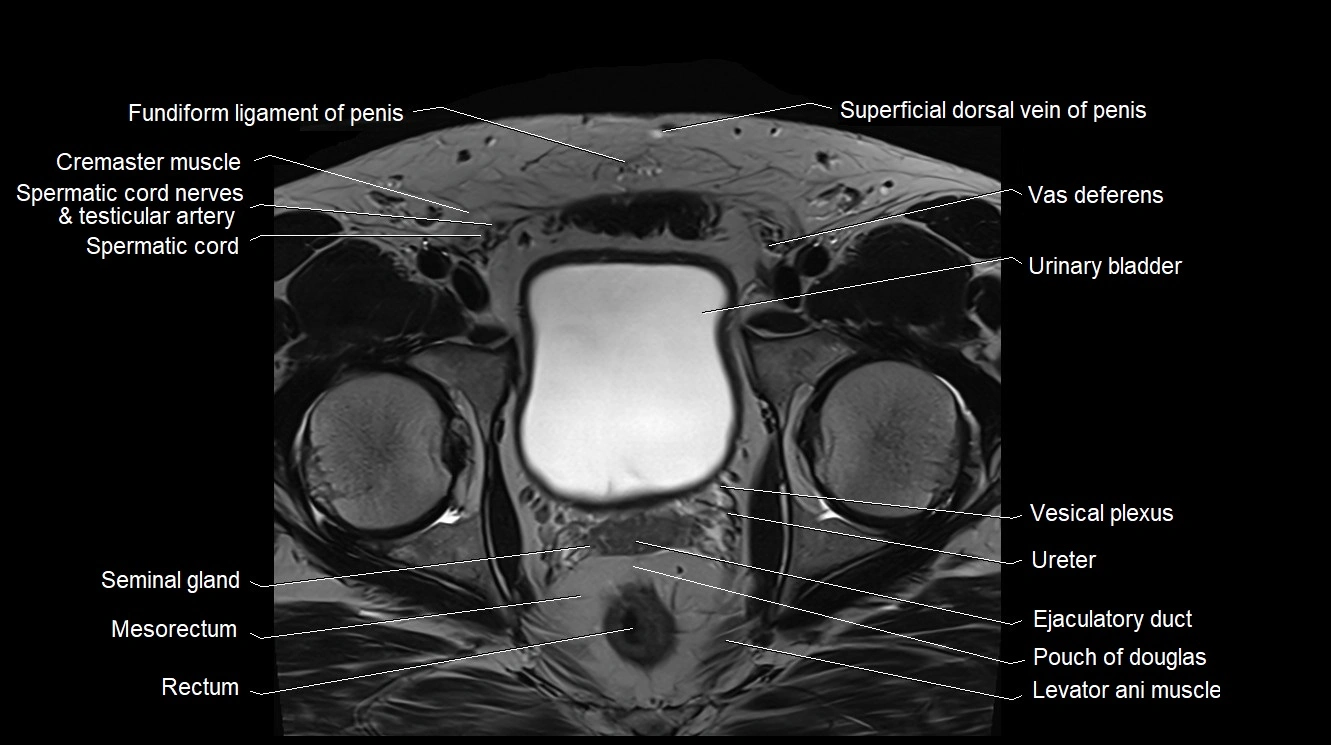

MRI image